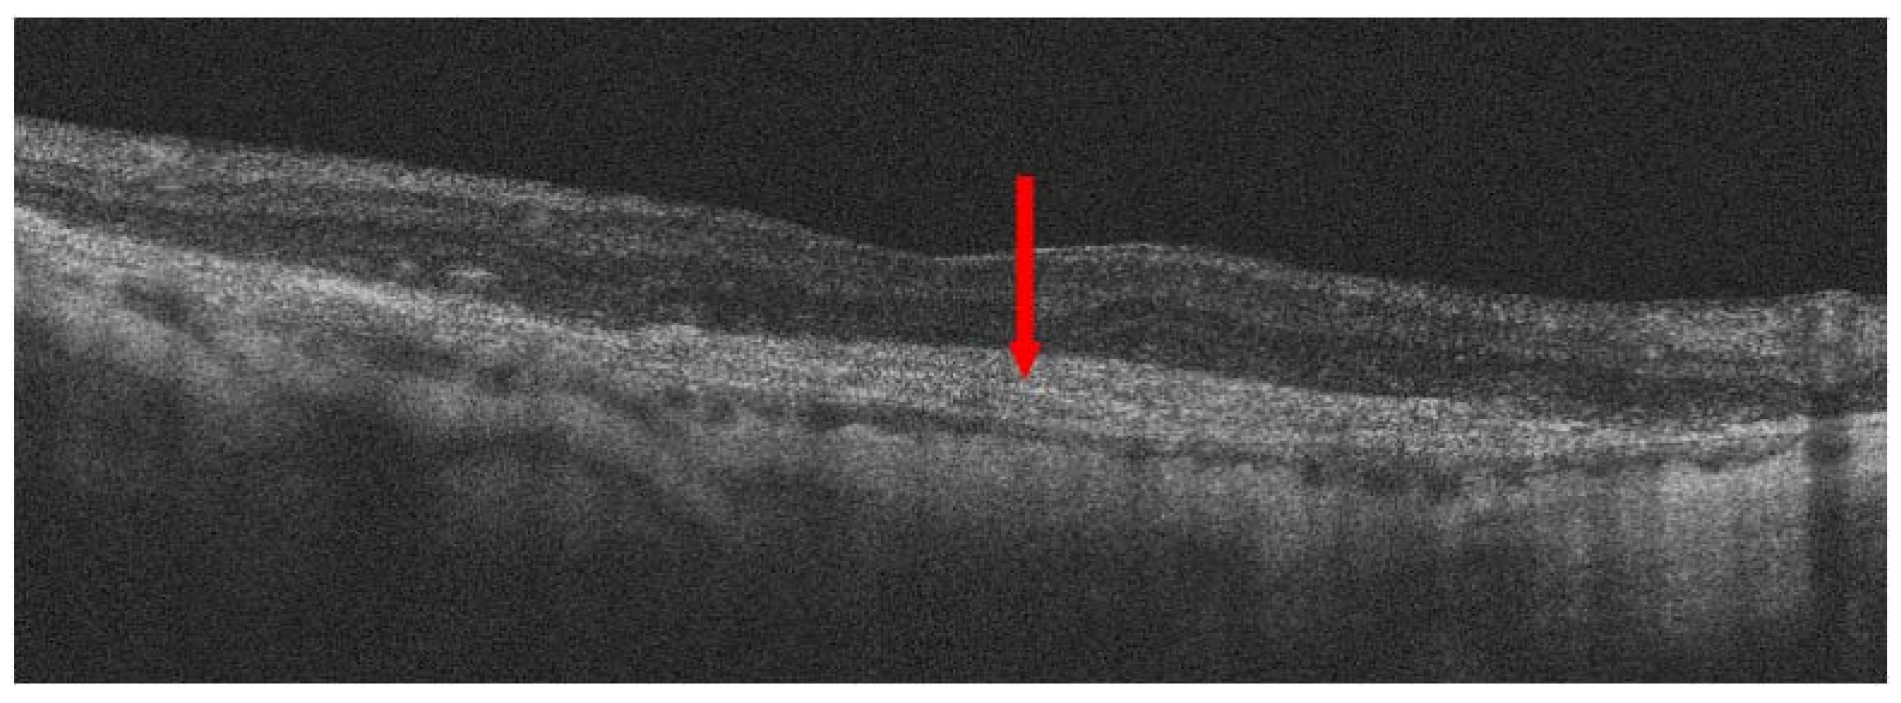

- Spaide, R.F.; Jaffe, G.J.; Sarraf, D.; Freund, K.B.; Sadda, S.R.; Staurenghi, G.; Waheed, N.K.; Chakravarthy, U.; Rosenfeld, P.J.; Holz, F.G.; et al. Consensus Nomenclature for Reporting Neovascular Age-Related Macular Degeneration Data: Consensus on Neovascular Age-Related Macular Degeneration Nomenclature Study Group. Ophthalmology 2020, 127, 616–636. [Google Scholar] [CrossRef]

- Hilely, A.; Au, A.; Freund, K.B.; Loewenstein, A.; Souied, E.H.; Zur, D.; Sacconi, R.; Borrelli, E.; Peiretti, E.; Iovino, C.; et al. Non-neovascular age-related macular degeneration with subretinal fluid. Br. J. Ophthalmol. 2021, 105, 1415–1420. [Google Scholar] [CrossRef]

- Hwang, C.K.; Agron, E.; Domalpally, A.; Cukras, C.A.; Wong, W.T.; Chew, E.Y.; Keenan, T.D.L.; Group, A.R. Progression of Geographic Atrophy with Subsequent Exudative Neovascular Disease in Age-Related Macular Degeneration: AREDS2 Report 24. Ophthalmol. Retin. 2021, 5, 108–117. [Google Scholar] [CrossRef]